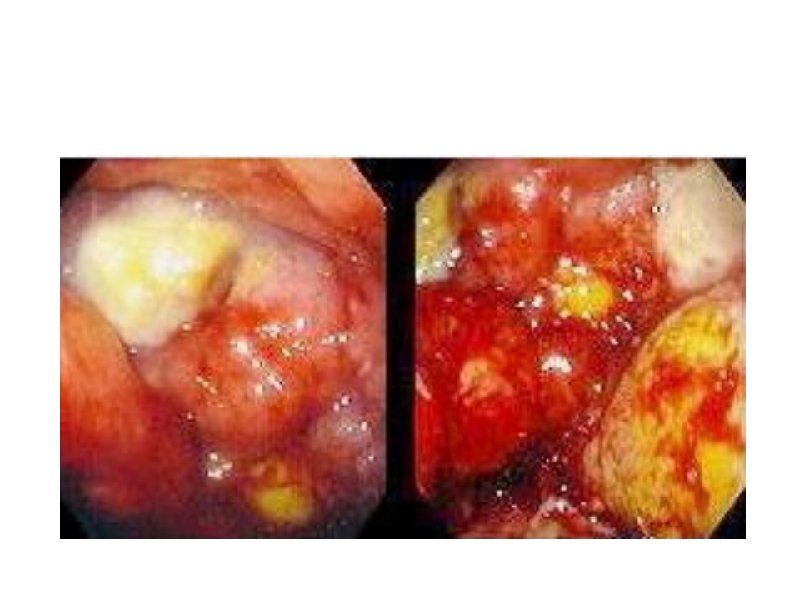

Наружные лимфоузлы при неходжкинских лимфомах